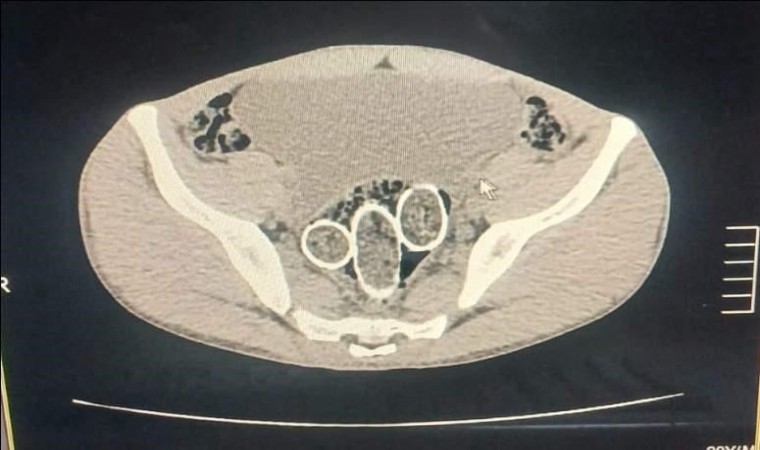

Denizli’de polisin düzenlediği uyuşturucu operasyonunda gözaltına alınan 5 şüpheliden 2’sinin yapılan iç beden muayenesinde rahim ve mideye saklanmış 320 gram uyuşturucu madde ele geçirildi.

Denizli İl Emniyet Müdürlüğü Narkotik Suçlarla Mücadele Şube Müdürlüğü ekiplerince, uyuşturucu ticaret yapan şahıs veya organizasyonların yakalanmasına yönelik operasyon düzenlendi. Düzenlenen eş zamanlı operasyonlarda 5 şüpheli şahıs yakalanırken, iki şahsın yaptırılan iç beden muayenesinde ve kullandıkları iki araçta yapılan incelemelerde rahimde ve midede uyuşturucu madde tespit edildi.

Operasyonda 6 parça halinde 320 gram metamfetamin maddesi, 1,6 gram afyon sakızı maddesi, uyuşturucu madde ticaretinden elde edildiği değerlendirilen 114 bin 430 TL, 12 bin 595 Euro, 300 dolar, 1 adet sahte pasaport ele geçirildi. Ayrıca yakalanan şüpheli şahıslardan 1 şahsın 6 yıl 8 ay kesinleşmiş hapis cezası ve 16 bin 600 TL adli cezası ile arandığı tespit edildi.